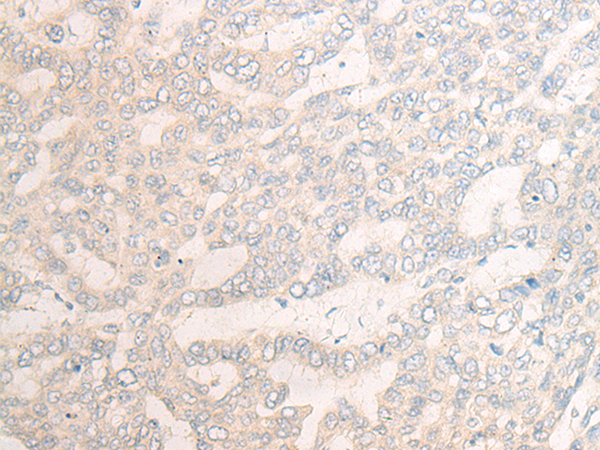

分类: 科研抗体货号: P13146别名: SCP; SPC; UCNIII应用: WB,IHC反应种属: Human